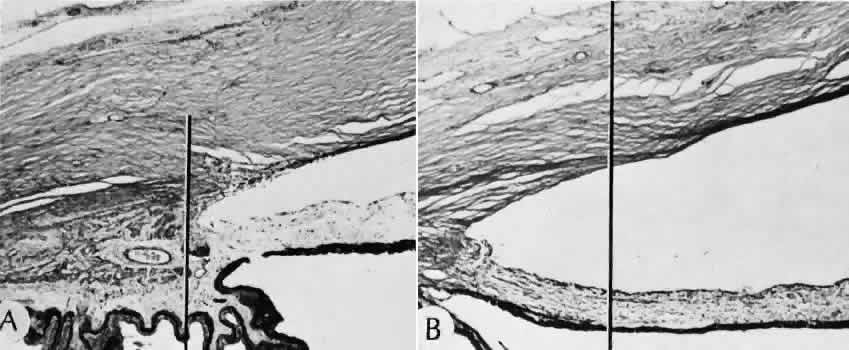

Misplacement of an anterior segment incision too far anteriorly into the cornea may create an unacceptable degree of scarring or astigmatism, whereas misplacement too far posteriorly (Fig. 25) may cause the incision to enter the ciliary body instead of the anterior chamber, an especially serious event in glaucoma filtering procedures. Misplacement oflimbal sutures (Fig. 26) may cause anterior wound gaping if placed too far posteriorly or posterior wound gaping if placed too far anteriorly. A deep suture may enter the anterior chamber and lead to wicking and a flat anterior chamber postoperatively. A suture placed at different depths in the two sides of the wound results in faulty apposition of the wound edges.

Fig. 26. Complications related to a limbal wound. A. The posterior edges of the limbal wound are poorly apposed. Incarcerated vitreous can be identified in the wound at higher magnification, (inset). The cut edges of Descemet's membrane are widely displaced (d). (Hematoxylin-eosin stain; A, × 54; inset, × 101.) B. Vitreous is incarcerated into the wound immediately anterior to an area of total anterior synechiae. C. At higher magnification, vitreous can be clearly identified in the wound. A fibrous membrane is present posterior to Descemet's membrane. The arrows indicate the cut edges of Descemet's membrane. (Periodic acid/Schiff stain; B, × 16; C, × 40.)